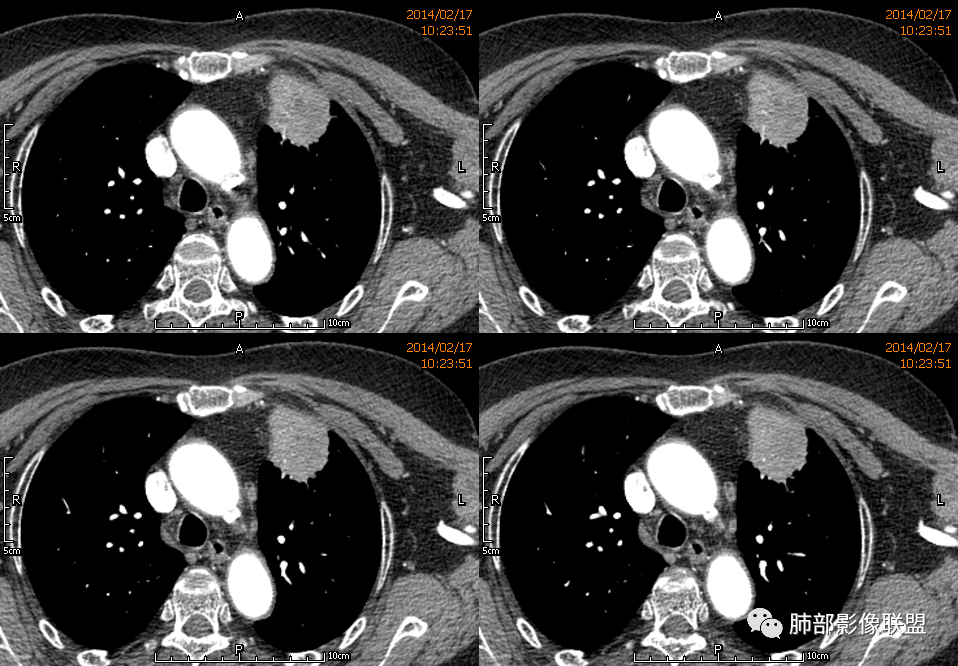

3.病灶密度不均,中央坏死液化并见气泡影,支气管及血管贴边进入,较均匀环形强化(显示多层结构),未见明确壁结节。

4.肺门纵隔未见肿大淋巴结。

1.块影不规则,未见分叶、毛刺及张力,未见壁结节,肺门纵隔未见肿大淋巴结等,缺少肺腺癌的特征。

2.未见血管及支气管受累,用肺鳞癌不好解释,何况女性患者。

3.病灶易坏死液化,环形强化,支气管及血管贴边进入,“火焰”样边缘轮廓,更符合炎性块影的特点。

4.单发脓肿,临床中毒症状不重,短期多见于肺炎克雷比杆菌感染,亚急性病程的还应排除奴卡菌感染。